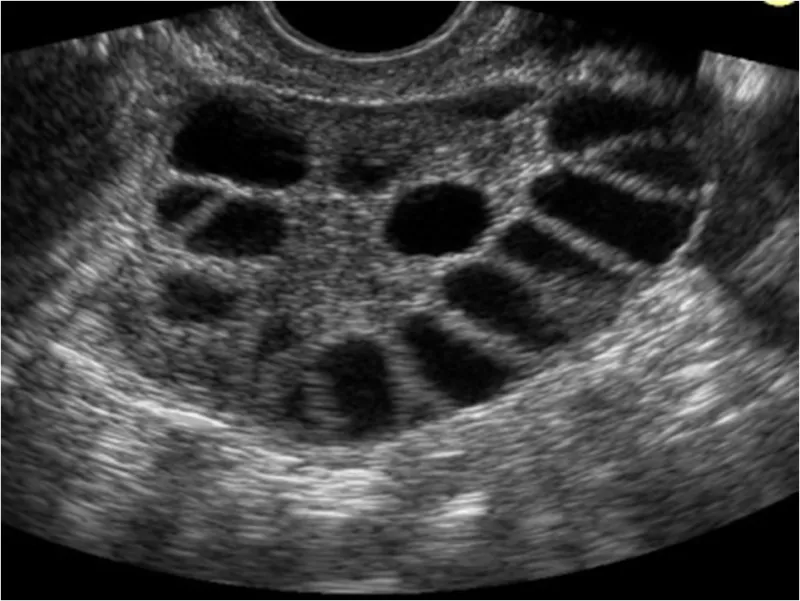

Mi is a :Policisztás ovárium szindróma?

Policisztás ováriumnak, azaz sok hólyagocskát tartalmazó petefészeknek nevezik azt, amikor a petefészekben (a tüszőrés zavarából kifolyólag számos kis tüsző indul növekedésnek, de ezek érése nem fejeződik be. Ez egy összetett hormonális betegség, mely a nemi hormonok termelésén túl (petefészek működési zavara) a szénhidrát anyagcsere zavarát is magában foglalja.

Normál esetben a petefészkekben számtalan igen apró éretlen és havonta peteéréskor egy-kettő 20 mm körüli nagyságú tüsző található.

A nőgyógyászati ultrahang is kimutathatja a PCO jelenlétét.